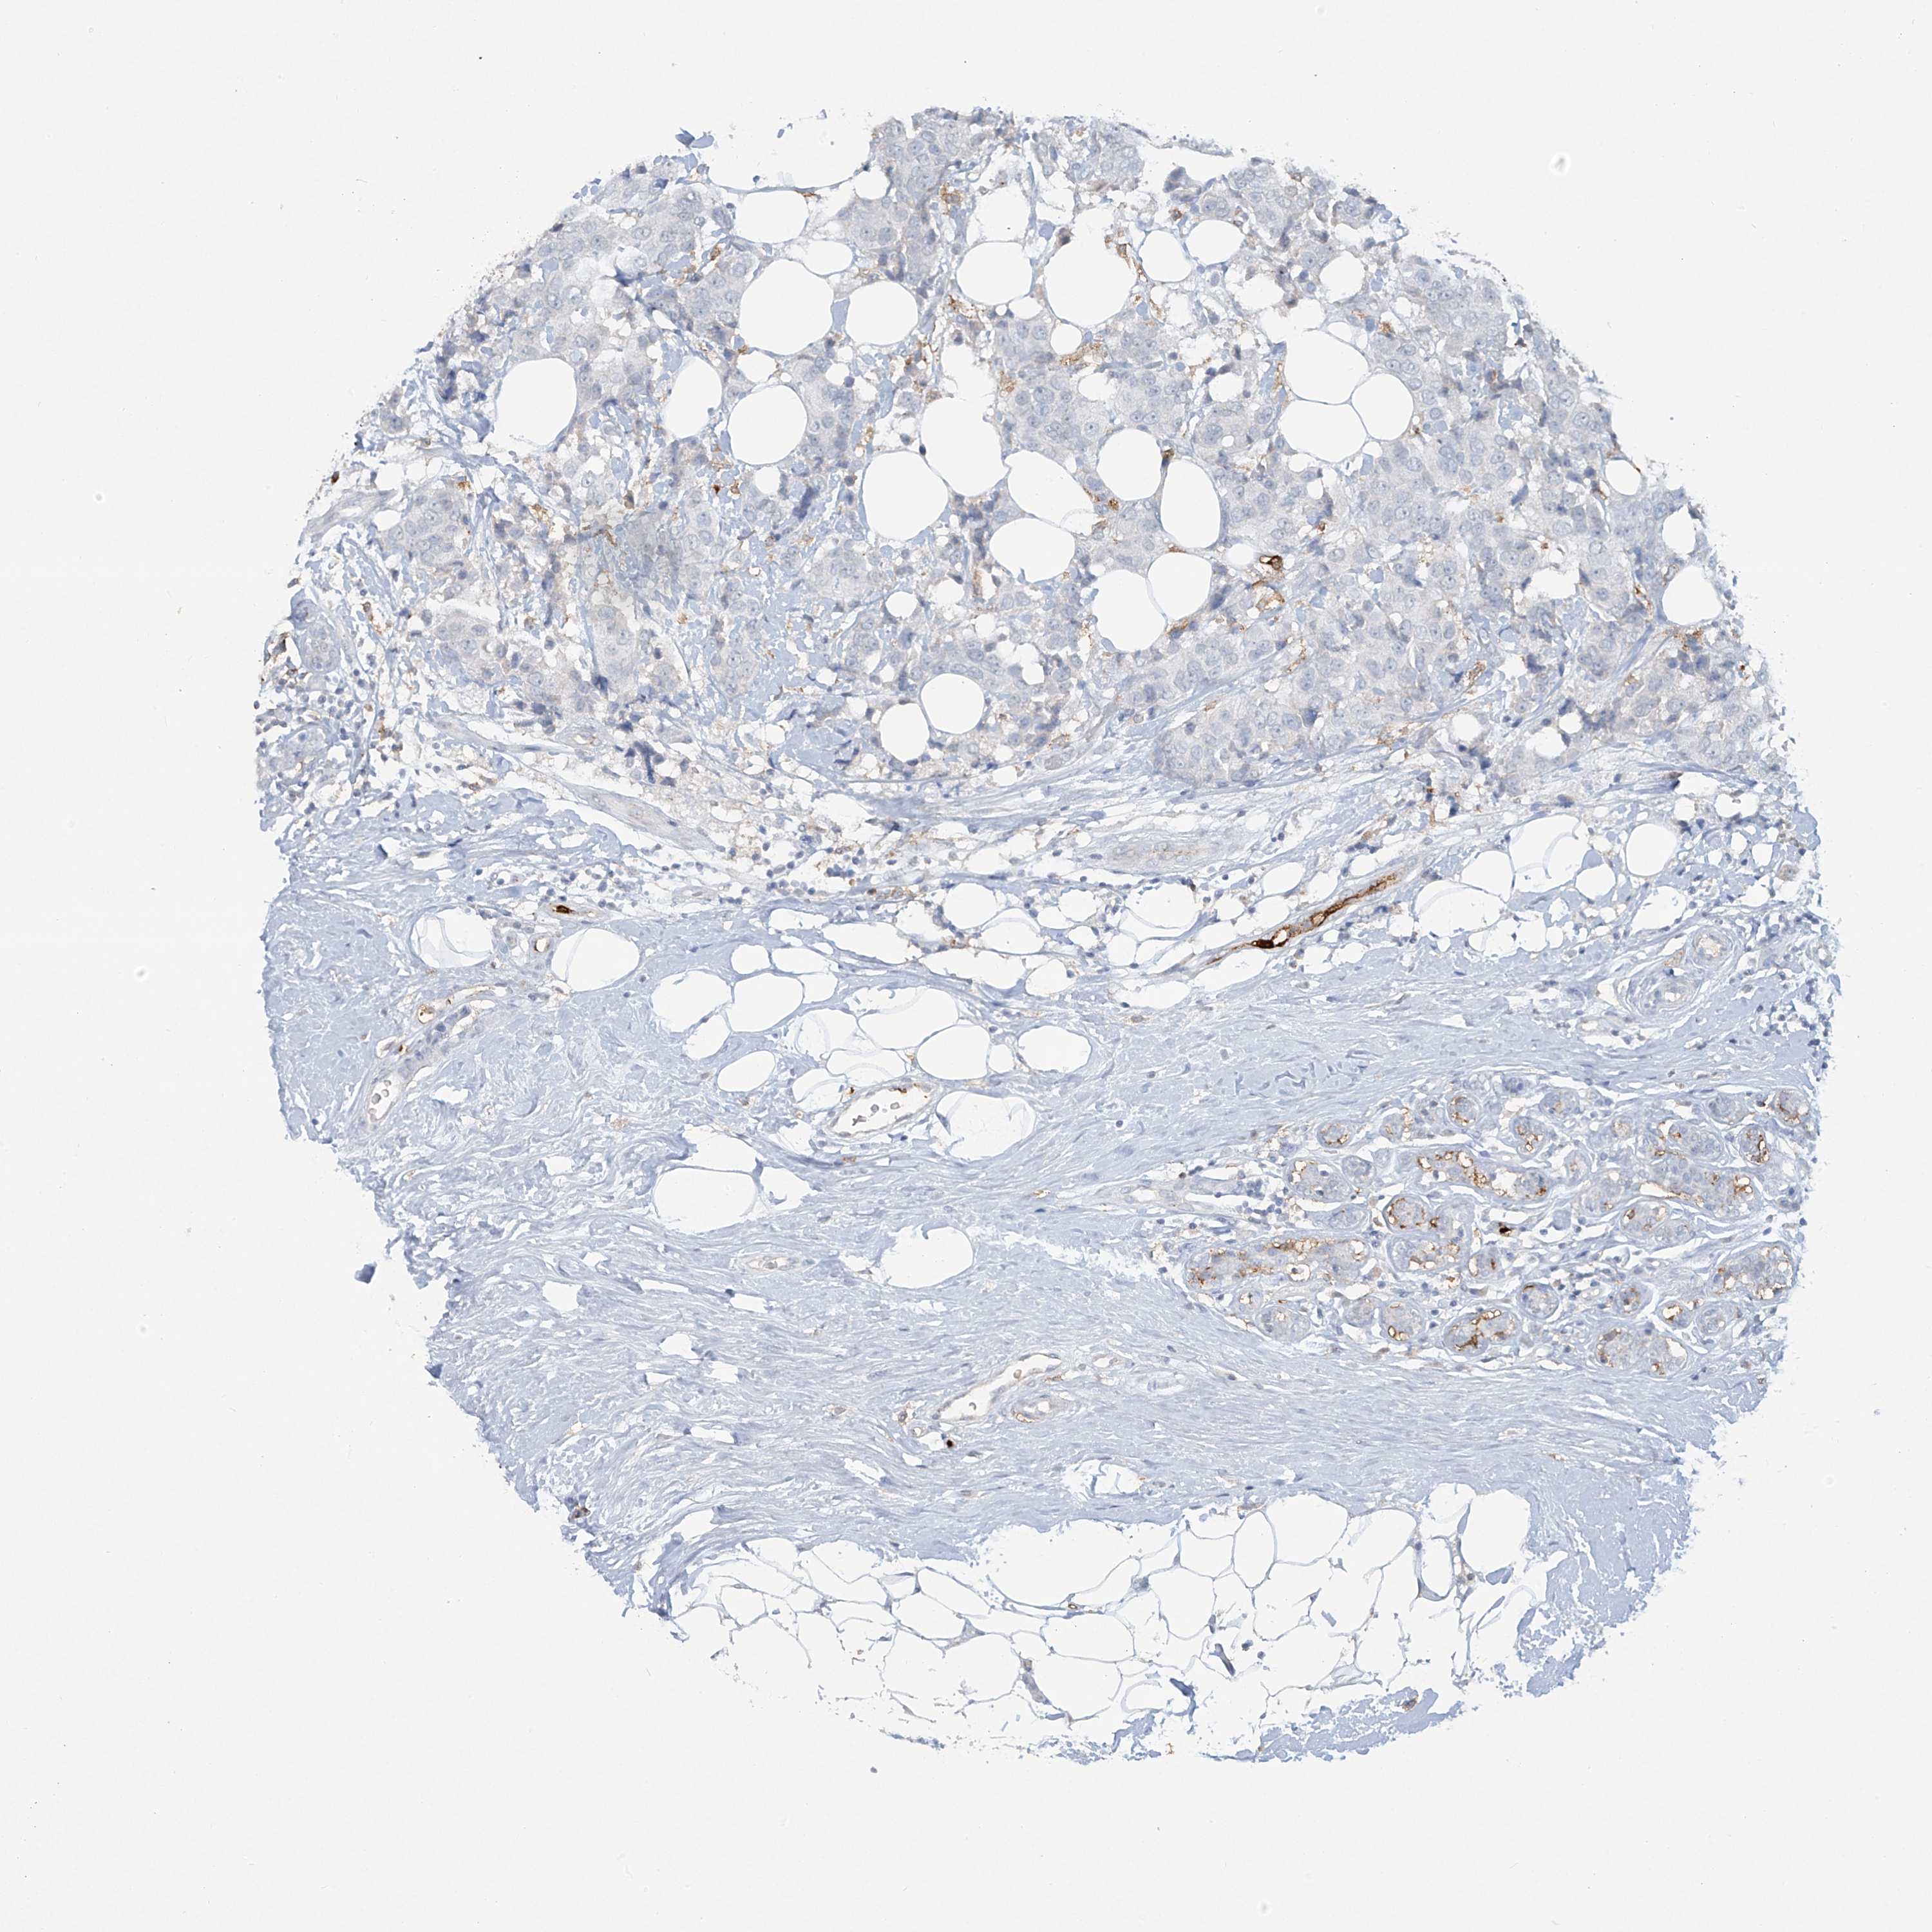

BRCA TCGA BRCA VALIDATION PROTEIN EXPRESSION

ANTIBODIES

AND

VALIDATION